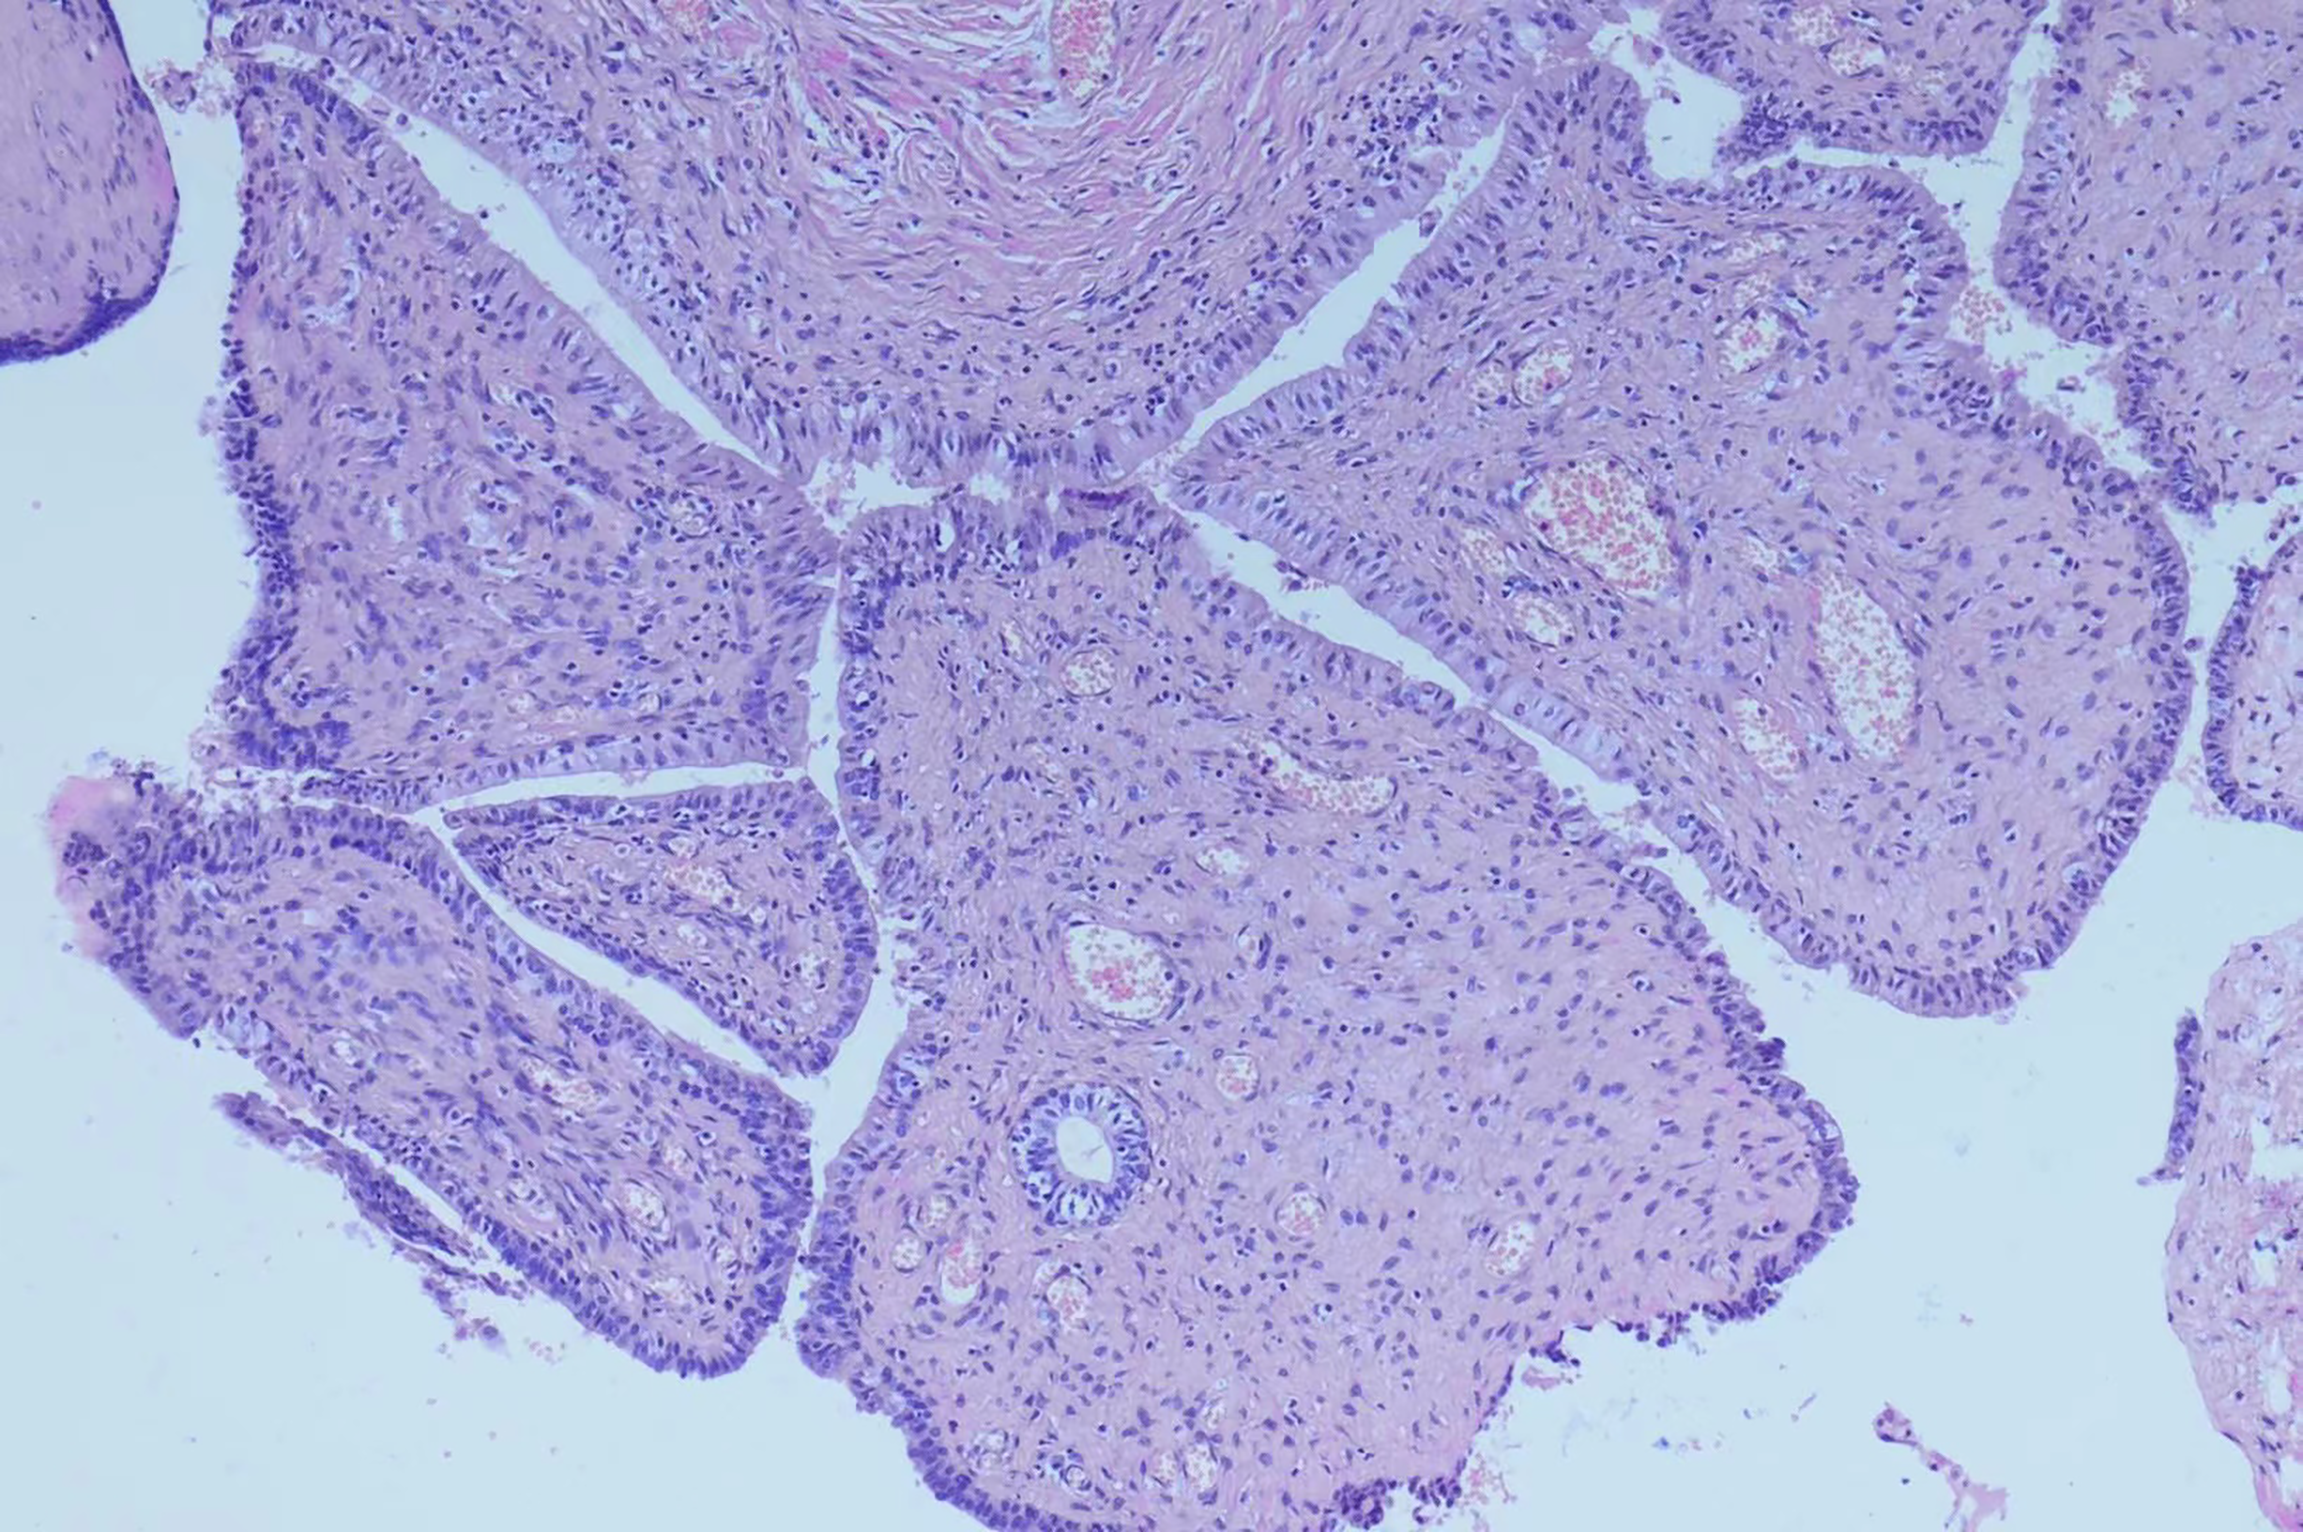

Figure 2

Microscopically, tumor histology revealed fibrous components (mostly) and epithelial components, without atypia. Immunohistochemical results were:CK (+), Vim (+), GATA3 (+), PAX -8(+), CD34 (vessel+), bcl- 2(+), SMA (-), ER (mesenchy me+), PR (mesenchyme+), ki67(+, about 1%).